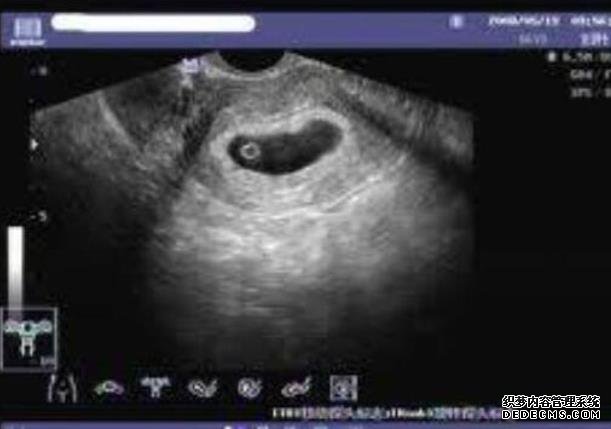

如果要谈到试管婴儿的话,可能很多人都认为这是一个比较专业的话题,其实大多数的人会发现,我们在各个不同的时间段做试管婴儿这项手术的时候,他们也会需要各种不同的胚胎。当然在无锡人民医院试管婴儿手术进行过程当中,可能很多人问到的问题最多的,也就是这个关于试管婴儿的手术情况,大家不妨一起来了解一下,我们也可以对所有的胚胎等级进行全面划分和了解。

一级胚胎和二级胚胎

从无锡人民医院的胚胎情况来看,一级胚胎的细胞数或者是发育的天数基本上都是合适的,那么通常情况下有7个细胞到9个细胞到9个细胞细胞的大小全部都是均匀的,而且碎片通常都是小于5%,这种情况下整个胚胎也就会有所差别,二级胚胎的细胞数和发育的天数基本上是合适的,有6个细胞到10个细胞细胞的大小全部都可以忽略不计,碎片在5%~20%之间。

三级胚胎和4级胚胎

我们在选择做试管婴儿手术的时候,你会发现三级胚胎和四级胚胎也是有所不同的,三级胚胎的细胞数和发育的天数明显呈现着不符合的状态,细胞的大小明显不均匀,碎片在21%~50%左右,如果是4级胚胎的话,细胞的数量或者是整个发育的天数也会呈现着明显不符合,细胞的大小有着严重不均匀的情况,而且它们的碎片会在50%左右,所以大家在这方面一定要格外注重。

囊胚期胚胎等级如何划分?

在人民医院选择做试管婴儿这项手术的时候,在囊胚期间如果要对所有的等级进行划分,那么这种情况下采用的全部都是人类囊胚分级系统,也就是说可以从整个囊胚的扩张程度来进行了解,有各种不同的细胞团来进行滋养,而且要在各个不同的方面进行评价,整个囊胚腔的扩张程度也分为很多不同的等级,等级越高也就越好,对于三级以上的囊胚,那么后期会有各种不同的字母,分别代表着内部的细胞团或者是滋养层的等级。